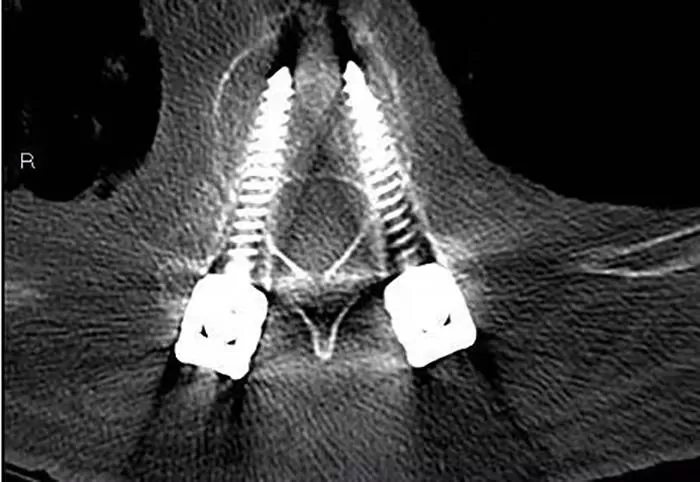

Postoperative imaging

3D printing surgery can effectively improve the success rate of thoracic and spinal pedicle screw implantation. 3D printing technology provides a new treatment approach for complex spinal cutting and correction surgeries such as posterior pedicle screw implantation in cervical and upper thoracic vertebrae, postoperative scoliosis protrusion deformities, and chronic thoracolumbar fractures. 3D printing technology not only reduces operational difficulty and risk, but also reduces operation time, achieves foresight and precision, and provides personalized solutions. It also brings good news for patients to relieve pain.